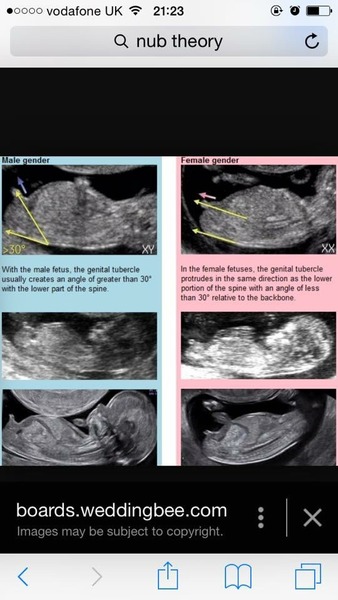

Cuppa: if nub theory is correct, that looks like a girl nub.

NoArmarni you can see a nub?! We were thinking girl, would save us a lot of money on baby clothes. We will see in a couple months if nub theory is right, would be really cool if it was.

Nub theory explained here

NoArmarni I still can't figure out what is nub and what isn't but that picture is the best explanation I've seen.